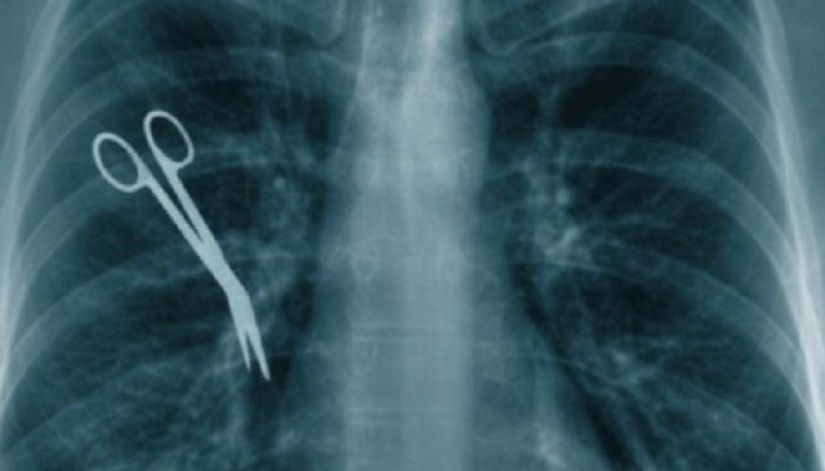

8. Leaving surgical instruments inside the patient.

I really want to believe that this is a myth. But in fact, this does not happen so rarely. Forceps, scalpels, scissors, and even more imposing instruments are forgotten in patients. Worst of all, the abandoned item may not show itself at all for years.